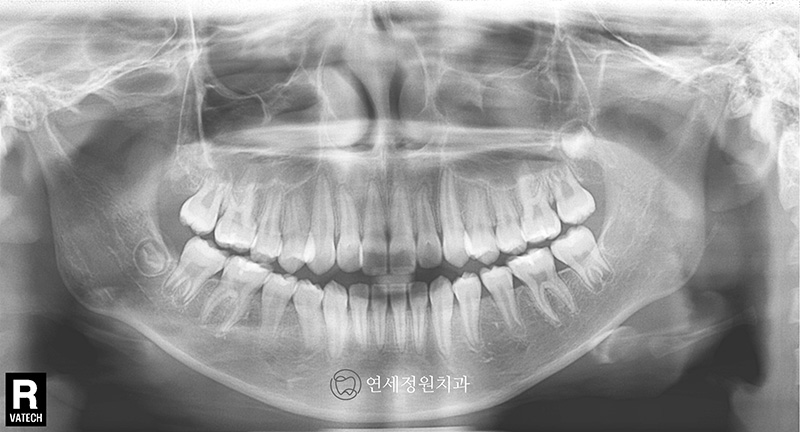

2019년 내원하였을 때 이미 유치는 다 빠지고 영구치가 다 올라온 상태였으며, 측면 엑스레이 상에서 전치부 교합은 좀더 안정적으로 잘 유지되고 있었습니다. 이제 영구치가 다 올라와서 2차교정을 시작해도 되는 시기였으나, 환자가 6개월 뒤 캐나다로 유학을 갈 예정이어서 교정 시작 시기는 환자분 스케줄에 맞춰서 시작하셔도 된다고 설명을 드렸습니다.

그리고 얼마 전 오랫만에 저희 연세정원치과로 환자분께서 찾아왔을 때는 이미 키가 거의 170cm가 다 된 숙녀가 되어있었습니다 :) (원래 악세서리는 다 제거하고 찍어야 하지만... 엑스레이 상에서도 여기저기 피어싱이 보이네요 ㅎㅎ) 방학이라 한국에 잠시 들른 동안 정기 검진을 받으러 왔는데, 위 앞니 하나가 틀어져 있고 입이 살짝 돌출이라 2차 교정 상담을 하셨으나, 한달 뒤 출국 일정 때문에 부분교정을 하기에도 시간은 부족한 상태였습니다.

2024년 7월